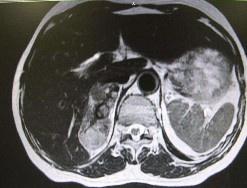

腎上腺腫瘤

628健康網為您分享有關腎上腺腫瘤的癥狀,腎上腺腫瘤的治療方法,腎上腺腫瘤的預防知識,腎上腺腫瘤的癥狀圖片,腎上腺腫瘤...